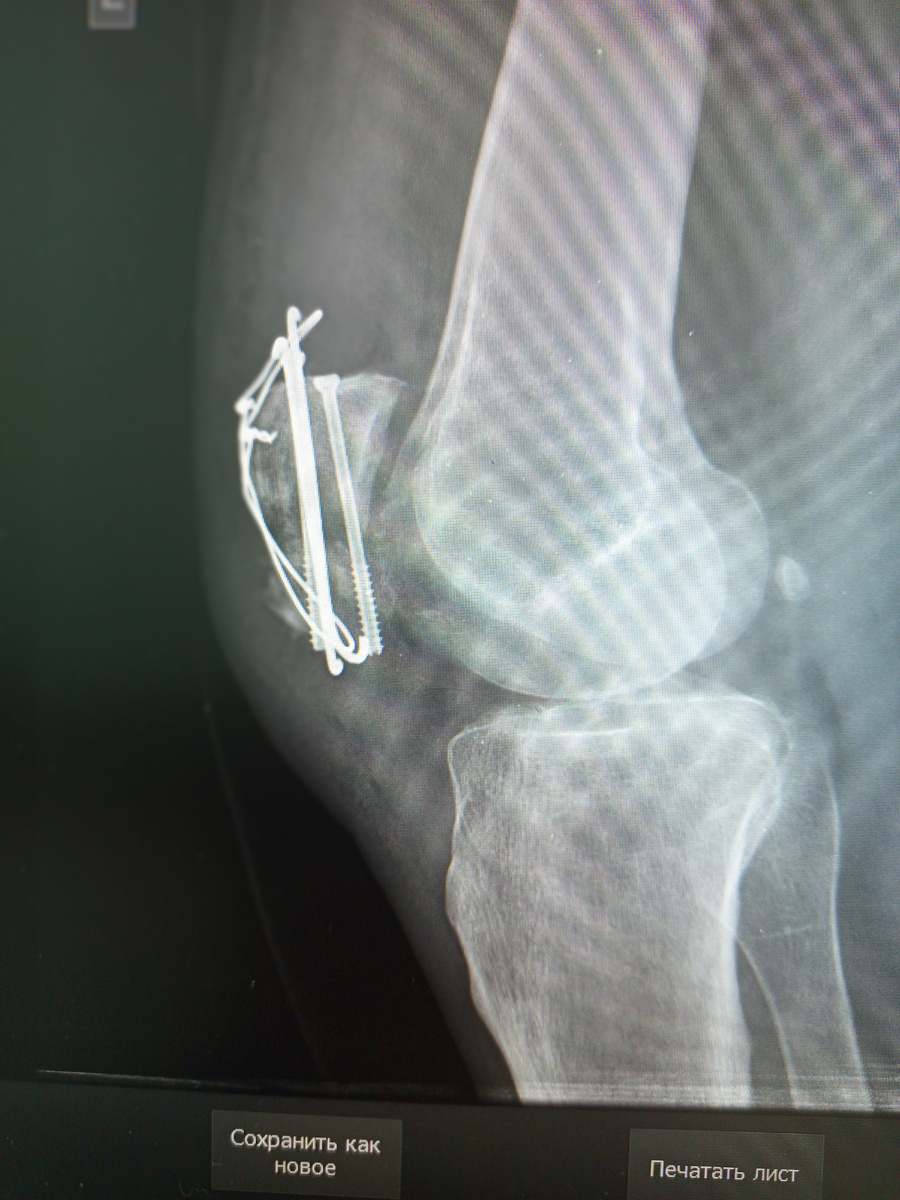

Мужчина пришел , на контроль конструкции , стоящей уже два месяца. Был у него сломан надколенник. Выполнили металлоостеосинтез по Веберу.

МОС по Веберу